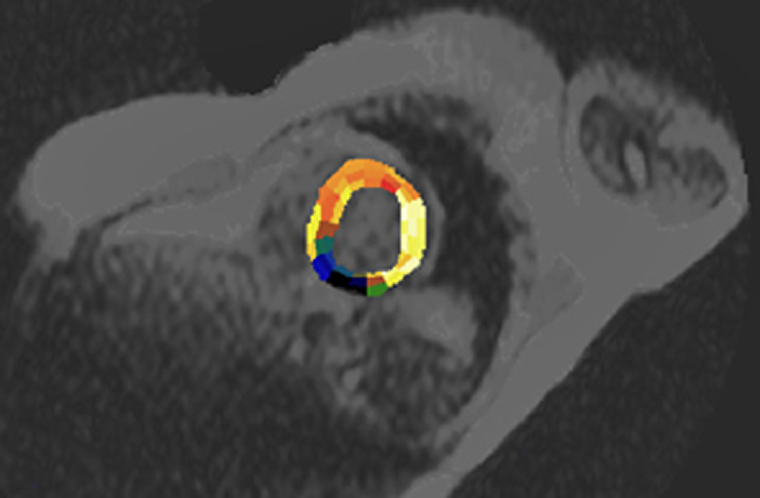

Figura 16-11:

In this case, the heart is semi-automatically divided into ROIs which follow the supply area of the coronary arteries. The pa­ra­met­ric image represents the cross-cor­re­la­tion coefficient (CCC) calculated one week after co­ro­na­ry in­farc­tion (dark area). See also Chapter 14.